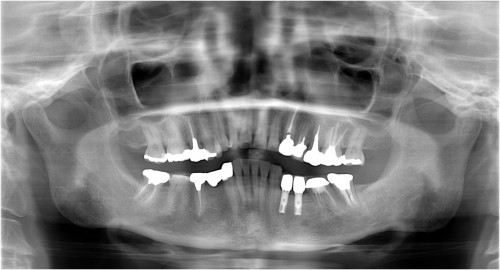

術前

抜歯後

埋入前(抜歯後約6ケ月)

上記、拡大写真

インプラント埋入直前

インプラント埋入時

同拡大

支台装着

被せ物装着

同全体写真